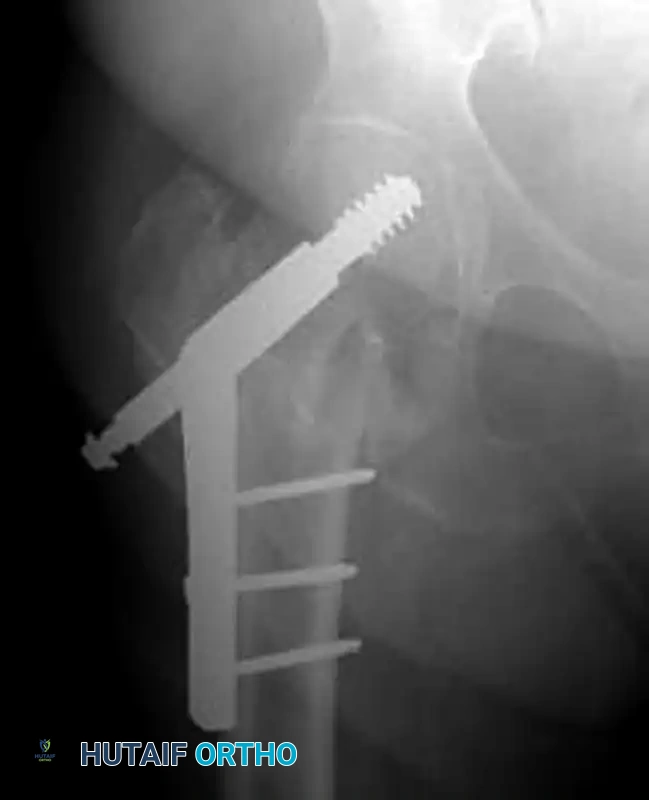

صور إشعاعية توضح نجاح التثبيت

فيما يلي مجموعة من الصور الشعاعية التي توضح الشكل النهائي للمسمار النخاعي داخل عظمة الفخذ بعد اكتمال الجراحة بنجاح:

تعتبر تقنية المسمار النخاعي هي الأحدث والأكثر تفضيلاً، حيث يتم إدخال دعامة معدنية (من التيتانيوم أو الفولاذ الطبي) داخل التجويف النخاعي لعظمة الفخذ، مما يوفر دعماً داخلياً قوياً للغاية.